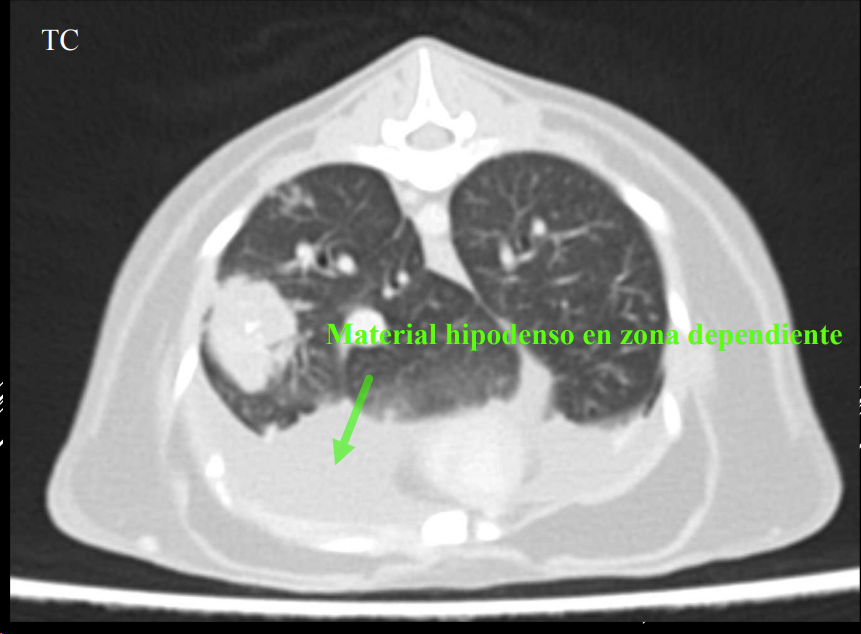

3. Alteraciones de anchura del mediastino craneal

- En perros: anchura < 2x VT.

- En gatos: anchura ≈ VT.

- En braquicéfalos/obesos puede verse mayor (grasa mediastínica).

- Generalmente en gatos es por un linfoma.

Causas:

- Derrame mediastínico.

- Masas mediastínicas (craneodorsales, hilares, caudodorsales, caudoventrales, craneoventrales).